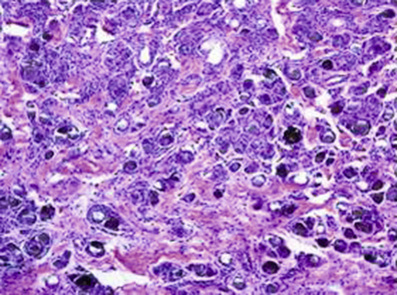

○ Linear (Fig. 7-8)

♦ IgG and C3: bullous pemphigoid, lichen planus pemphigoides, EBA, cicatricial pemphigoid, anti-p200, anti-p105, and bullous SLE

➔ NEED further studies to distinguish!!!